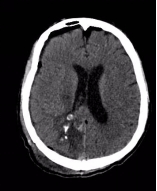

△术后头颅CT显示畸形团切除彻底

手术团队奋战8小时,终于在少量出血的情况下完整切除脑动脉畸形,并清除颅内血肿。